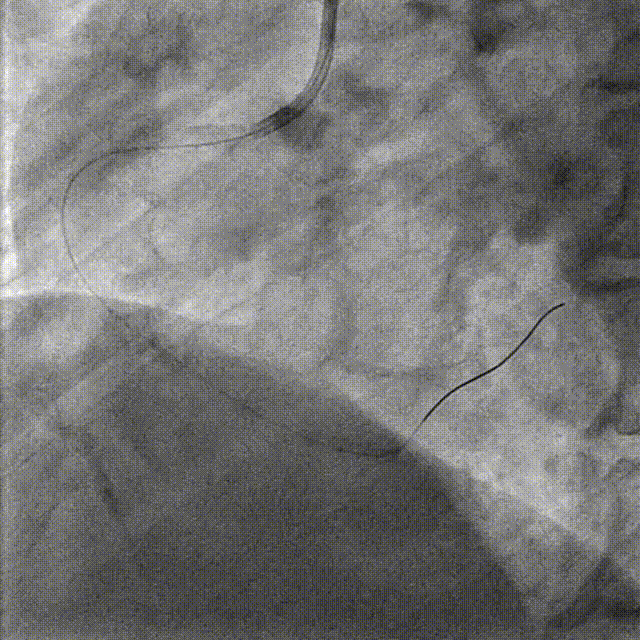

Lesion Preparation Cutting balloon 2.75*10mm @ 14atm

DCB Angioplasty DCB 2.75*25mm @ 8atm, 60s